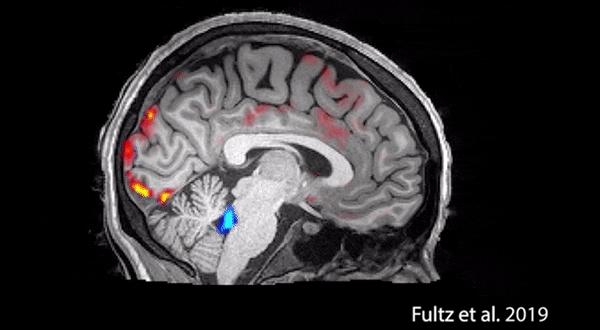

在波士顿大学的新研究中,我们在睡觉的时候,脑子里会发生一些不可思议的事情。

睡觉后,大脑中的神经元会平静下来,但是,供给大脑的血流会继续流动。

接着,负责大脑废物的胶质细胞开始工作,间质间隙增大,从而加速代谢物的清除。

白天让我们和孩子们更好地完成工作和学习!

假如娃娃在熬夜,这个过程就会受到影响。

从长远来看,晚上大脑很难恢复到最佳状态,白天的学习和生活质量也会降低,形成恶性循环,对孩子在学习中的表现影响越来越大。